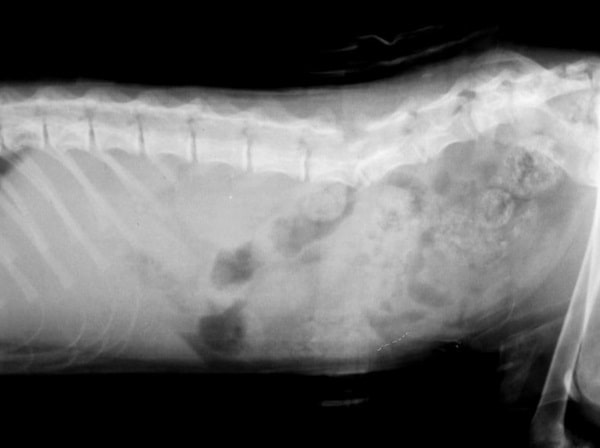

Хребта

Перелом хребта — вкрай важке ушкодження, оскільки до нього майже неминуче приєднується ушкодження спинного мозку (зазвичай це його контузія в момент травми та компресія через зміщення уламків хребців).

Залежно від ділянки травми в таких пацієнтів зазвичай порушується контроль тазових (у разі пошкодження грудопоперекового відділу хребта) або всіх чотирьох кінцівок (у разі пошкодження шийного відділу).

Важливо розуміти, що під час таких операцій хірург може забезпечити реконструкцію хребетного стовпа, але не тканини спинного мозку (СМ). Тому можливості відновлення втрачених функцій безпосередньо пов’язані зі ступенем початкового пошкодження СМ.

Ті провідні структури СМ, які не пошкоджені анатомічно, але тимчасово не функціонують через набряк і стискання, можуть з часом відновити свою функцію. У таких випадках пріоритетним завданням є максимально рання репозиція і стабілізація ушкодженого сегмента хребта (у цьому разі оптимальний термін операції — не більше ніж 24 години після ушкодження).

Шанси на відновлення неврологічних функцій у разі перелому хребта оцінюються з огляду на ступінь неврологічного дефіциту на момент операції і часу, що минув від травми до втручання. За відсутності глибокої больової чутливості і часу понад 24 години шанси на відновлення є мінімальними, але не нульовими, якщо не констатовано повний анатомічний розрив спинного мозку.

Для діагностики таких пацієнтів часто достатньо рентгенографічного обстеження, однак, для повноцінного планування операції зазвичай використовується комп’ютерна томографія (КТ), та в деяких випадках магнітно-резонансна томографія (МРТ).